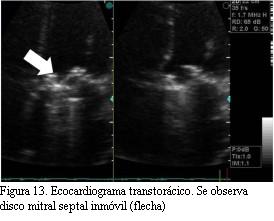

ETT (figuras 13 y 14): hipocontractilidad global, FEVI 40%.

Prótesis mitral mecánica con aumento de sus gradientes (gradiente máximo de 22 mmHg y medio de 15 mmHg). Área estimada 0,79 cm2.

Impresiona ausencia de movilidad de uno de los hemidiscos. Sin insuficiencia mitral.

Hipertensión pulmonar significativa.

ETE (figura 15): prótesis mitral mecánica con aumento de sus gradientes. Inmovilidad del disco septal con gran cantidad de trombos, algunos móviles. Insuficiencia mitral leve.